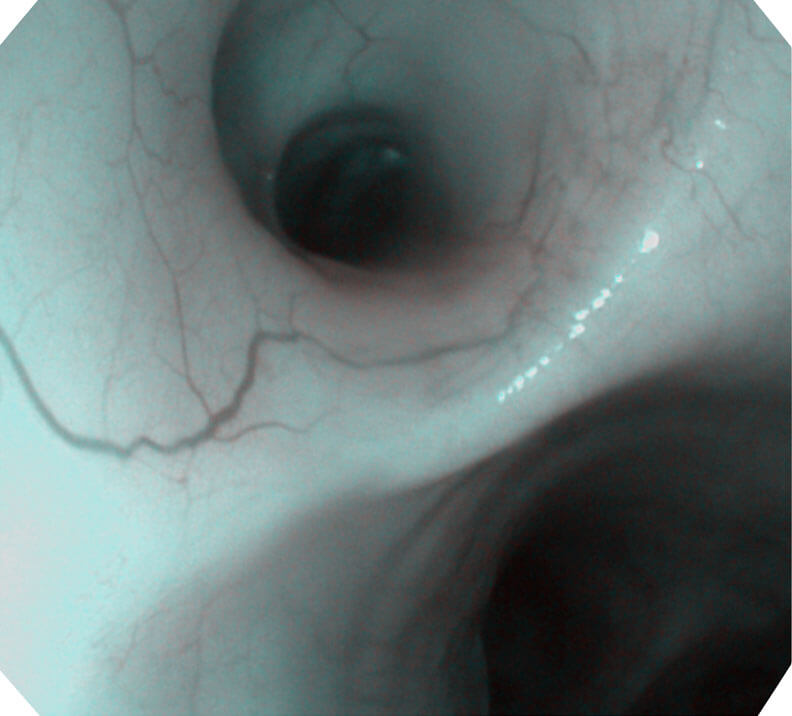

光电复合染色成像技术(VIST)是一种光学滤波和数字滤波相结合的染色成像技术,摒弃了滤光转轮而直接采用光谱组合的方案,加入了血红蛋白吸收高峰与次高峰的蓝紫光和绿光光谱,更有利于黏膜血管吸收,突显浅表层血管和中层血管的对比度,因而具备更高的图像对比度,有助于观察微细结构变化及病灶边界的观察。